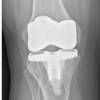

Introduction: Fracture of stems in primary total hip arthroplasty is a known complication and has been attributed to varus positioning, excessive weight of the patient, resorption of the femoral calcar and failure of the cement mantle. Fractures in uncemented revision femoral stems are rare and are attributed to reduction in proximal support either in the form of bone loss or an extended trochanteric osteotomy [ETO] against a distally well- fixed stem. Also, undersized stems and high BMI to increase the risk of stem fracture.

Case Report: We report 3 cases of uncemented revision stem fractures. Case 1 is a 77 year old male, Case 2 is a 71-year-old female, case 3 an 82-year-old male. All three patients had significant proximal femoral osteolysis. All three had an extended trochanteric osteotomy for the revision surgery. The hips had remained in-situ for 4, 2 and 5 years respectively prior to fracture.

Conclusion: When planning complex revision cases involving long uncemented stems, attention should be given to the above-mentioned variables. ETO non-union and proximal bone loss play an important role in stem fractures. Stem failure can occur irrespective of the make, and factors such as adequate stem size and good diaphyseal fit are non negotiable.